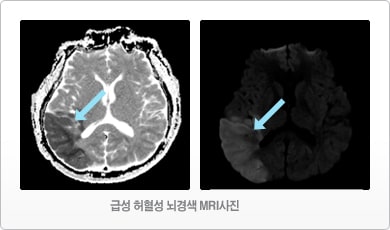

- MRI 검사 : CT 검사보다 자세한 뇌의 병변과 혈관 상태를 진단받을 수 있습니다.

- 급성 치료 : 혈전 용해제 : 혈전이 뇌혈관을 막아서 산소 및 영양 공급을 차단하는 경우, 약을 통해 혈전을 제거하거나 용해시킵니다.